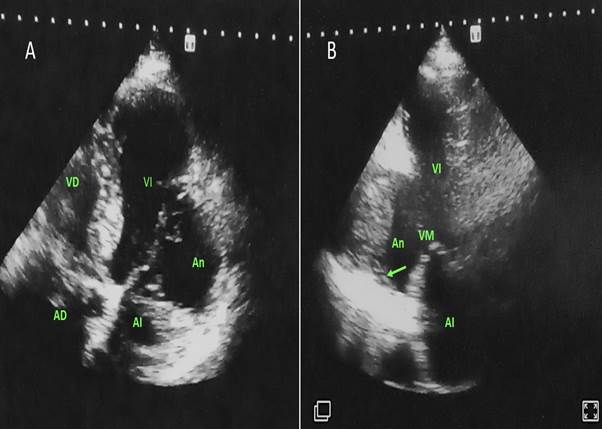

Ecocardiografía transtorácica bidimensional: Dilatación de cavidades izquierdas. Discinesia de pared inferior medio basal y anterolateral. Dilatación aneurismática extensa (39x30mm, Área 12.83cm2) en pared inferior y anterolateral en su porción medio-basal con presencia de trombos en su interior. (Figura 2A).

En la vista, dos cámaras aneurisma en pared inferior medio basal con trombo en su interior. (Figura 2B).

Las imágenes ecocardiográficas de este caso mostraron un aneurisma de pared inferior y lateral de grandes dimensiones con imagen de trombo en su interior, que como describe la literatura10 se presenta con poca frecuencia.